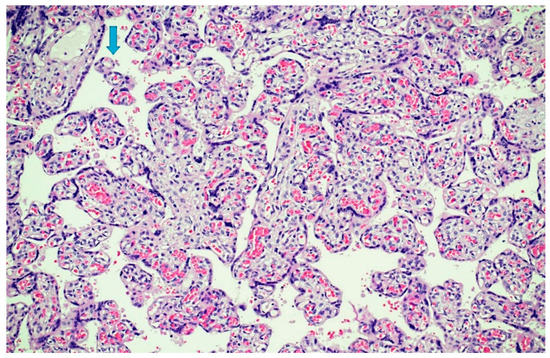

- Sheffield, J.S.; Sanchez, P.J.; Wendel, G.D., Jr.; Fong, D.W.I.; Margraf, L.R.; Zeray, F.; McIntire, D.D.; Rogers, B.B. Placental histopathology of congenital syphilis. Obstet. Gynecol. 2002, 100, 126–133. [Google Scholar] [PubMed]

- Qureshi, F.; Jacques, S.M.; Reyes, M.P. Placental histopathology in syphilis. Hum. Pathol. 1993, 24, 779–784. [Google Scholar] [CrossRef]

- Genest, D.R.; Choi-Hong, S.R.; Tate, J.E.; Qureshi, F.; Jacques, S.M.; Crum, C. Diagnosis of congenital syphilis from placental examination: Comparison of histopathology, Steiner stain, and polymerase chain reaction for Treponema pallidum DNA. Hum. Pathol. 1996, 27, 366–372. [Google Scholar] [CrossRef]